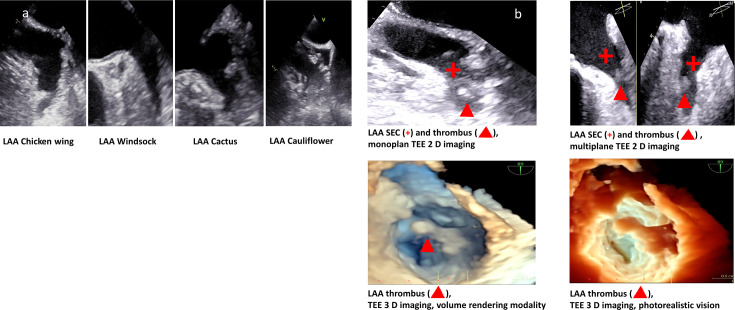

Methods: 185 patients (mean age 68±13 years, 33% female) were included in this prospective cohort study and underwent clinical evaluation, comprehensive transthoracic and transoesophageal echocardiography shortly after index event. LAA function and morphology were evaluated by monoplane/multiplane/speckle tracking strain and three-dimensional echocardiography. Combination of LAA thrombus and/or spontaneous echo contrast (SEC) was defined as TRC. An insertable cardiac monitor was implanted in all patients to detect subclinical AF.

Results: LAA function by novel LAA strain and LAA chicken wing were independent predictors of LAA thrombus (OR 0.9 (95% CI 0.8 to 0.95), p<0.01 and OR 2.5 (95% CI 1.1 to 5.8), p=0.04, respectively). LAA chicken wing and multilobate LAA were independent predictors of TRC (OR 2.3 (95% CI 1.2 to 4.5), p=0.01 and OR 2.2 (95% CI 1.2 to 4.2), p=0.02, respectively).LAA morphology was characterised as chicken wing in 79 (43%), windsock in 64 (34%), cactus in 35 (19%), cauliflower in 7 (4%) and multilobate LAA in 115 (62%) patients. LAA thrombus was found in 29 (16%), TRC in 123 (67%) and subclinical AF in 60 (32%) patients. Duration of subclinical AF >6 hours was associated with SEC and recurrent stroke and TIA.